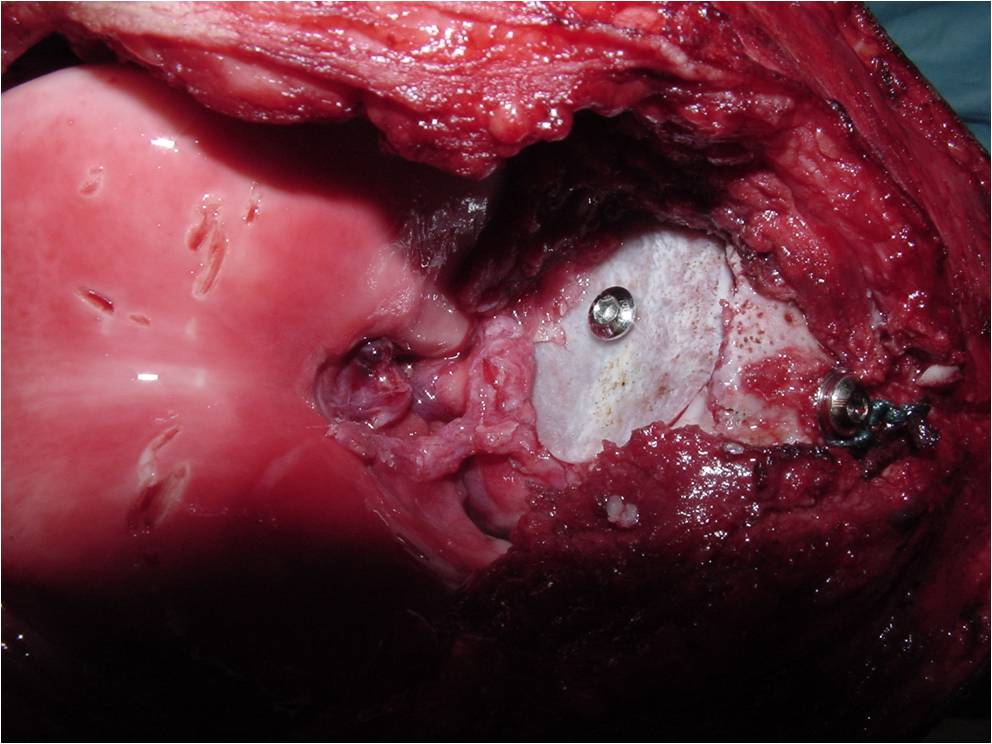

Treatment of a Chondroblastoma of Proximal Humerus with Intralesional Curettage Resection, Cryosurgery and Bone Grafting

- intralesional curettage resection and bone grafting most common treatment

- Cement and internal fixation may also be used to fill the defect after removal for selected patients

- Local adjuvants such as cryosurgery (liquid nitrogen application) may be considered to decrease the risk of local recurrence